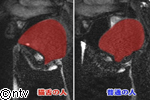

猫舌の治しかた Mriの動画で解説 Youtube